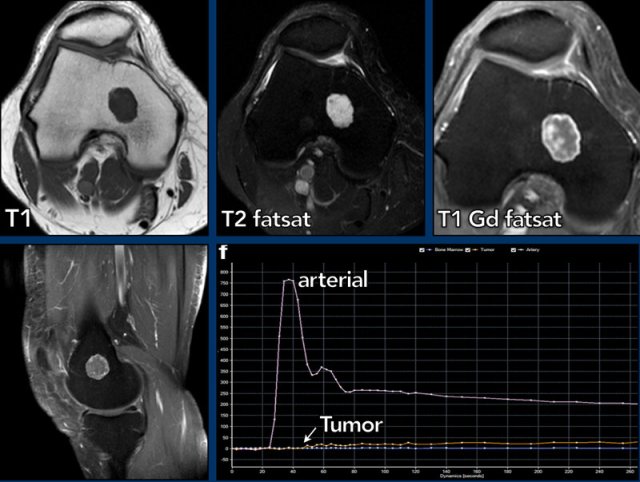

Images

There is a tumor of less than 2 cm in the distal femur metaphysis.

The lesion is hyperintense on T2, iso-intense on T1 and shows septonodular enhancement. There is no relation with the cortex. On the perfusion images (time intensity curve) the tumor shows slow enhancement, starting approximately 20 seconds post arterial enhancement.

This is an enchondroma and needs no follow up.